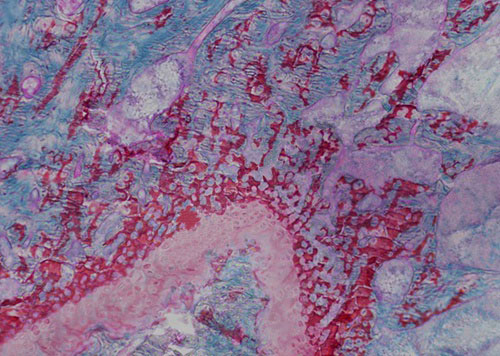

番紅O(Safranin O)-固綠(Fast Green),簡稱番紅固綠,是一種經(jīng)典的軟骨染色方法,因可以直觀反映關(guān)節(jié)軟骨、軟骨下骨及骨組織結(jié)構(gòu)而備受青睞。未脫鈣骨硬組織切片經(jīng)番紅固綠染色后,軟骨呈紅色, 成骨呈綠色。

實(shí)驗(yàn)結(jié)果展示:

未脫鈣大鼠骨番紅固綠染色